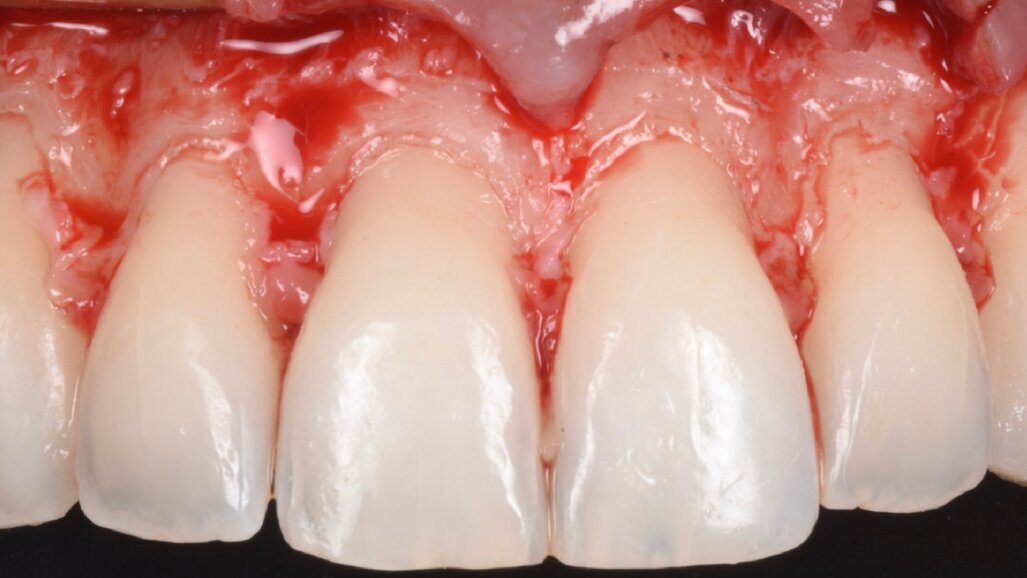

È perciò possibile durante la procedura di allungamento di corona clinica eseguire foto e video con un paziente completamente cooperativo. La prima procedura è la gengivectomia che ha lo scopo di eliminare la gengiva in eccesso e di esporre lo smalto dei denti altresì nascosto (Fig. 12). Una volta completata questa procedura si procede all’elevazione di un lembo a tutto spessore vestibolare che si estende per tutta la zona interessata dalla procedura. La mascherina chirurgica viene a questo punto ri-inserita in bocca per poter assistere la resezione della quantità di osso indicata per correggere la dimensione della zona di attacco sopra crestale (Fig. 13) La chirurgia ossea resettiva viene eseguita con l’ausilio di frese diamantate a palla con diverse dimensioni per le zone vestibolari e interprossimali oppure con strumenti piezo-elettrici. A procedura ultimata si può vedere come la nuova anatomia sia più consona all’attacco dei tessuti molli e favorente una miglior salute dell’attacco dento parodontale (Fig. 14).

Fig. 14_Rimodellamento osseo dopo chirurgia resettiva.